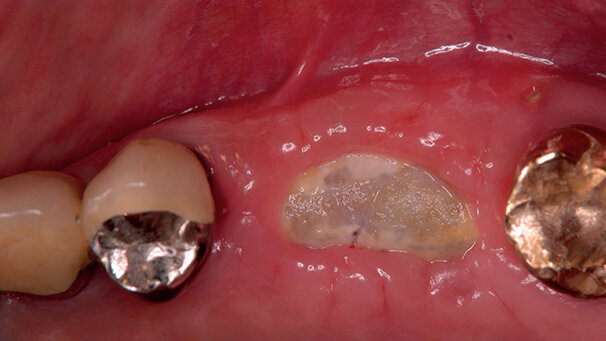

Dopo il sollevamento di lembi mucoperiostei, innesti di osso autologo o eterologo combinati con una matrice derivata della smalto (EMD) e/o plasma arricchito di piastrine (PRP) sono stati posizionati negli alveoli o sulle creste coperti da una membrana in dPTFE Cytoplast TXT200. I lembi sono stati riposizionati e suturati senza incisioni periostali di rilascio e la membrana è stata lasciata esposta non cercando di coprirla intenzionalmente.

La membrana è stata rimossa dopo 4-6 settimane senza anestesia in modo non chirurgico. Nei siti trattati sono stati inseriti impianti da 4 a 6 mesi dopo la rimozione della membrana.

Non è stata rilevata alcuna infiammazione o infezione nonostante le membrane fossero parzialmente esposte e la placca fosse presente sulla superficie in quasi tutti i casi. Alla rimozione della membrana si è osservato osso prematuro coperto da un tessuto soffice, liscio, rosso e non epitelizzato.

Il tessuto si è completamente riepitelizzato nell’arco di 1 mese. Gengiva cheratinizzata era presente in tutti i siti e alcuni casi ne mostravano un aumento. Tutti i siti hanno ricevuto impianti e clinicamente si è riscontrata osteointegrazione.